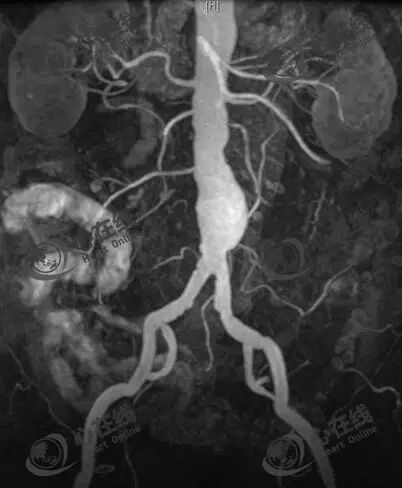

(3)CTA

常用于术前检查,以明确瘤体大小、近端瘤颈长度、成角、钙化及附壁血栓等解剖学形态。

上图可见瘤体巨大(>10cm),瘤颈扭曲